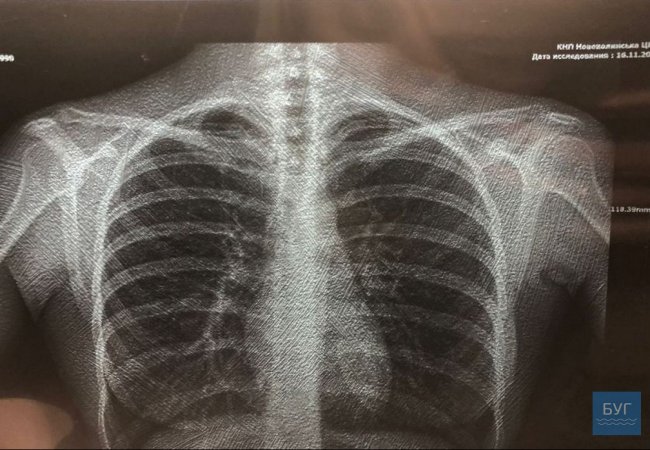

Фото на головній – знімок легень, зроблений на новому рентген-аппараті